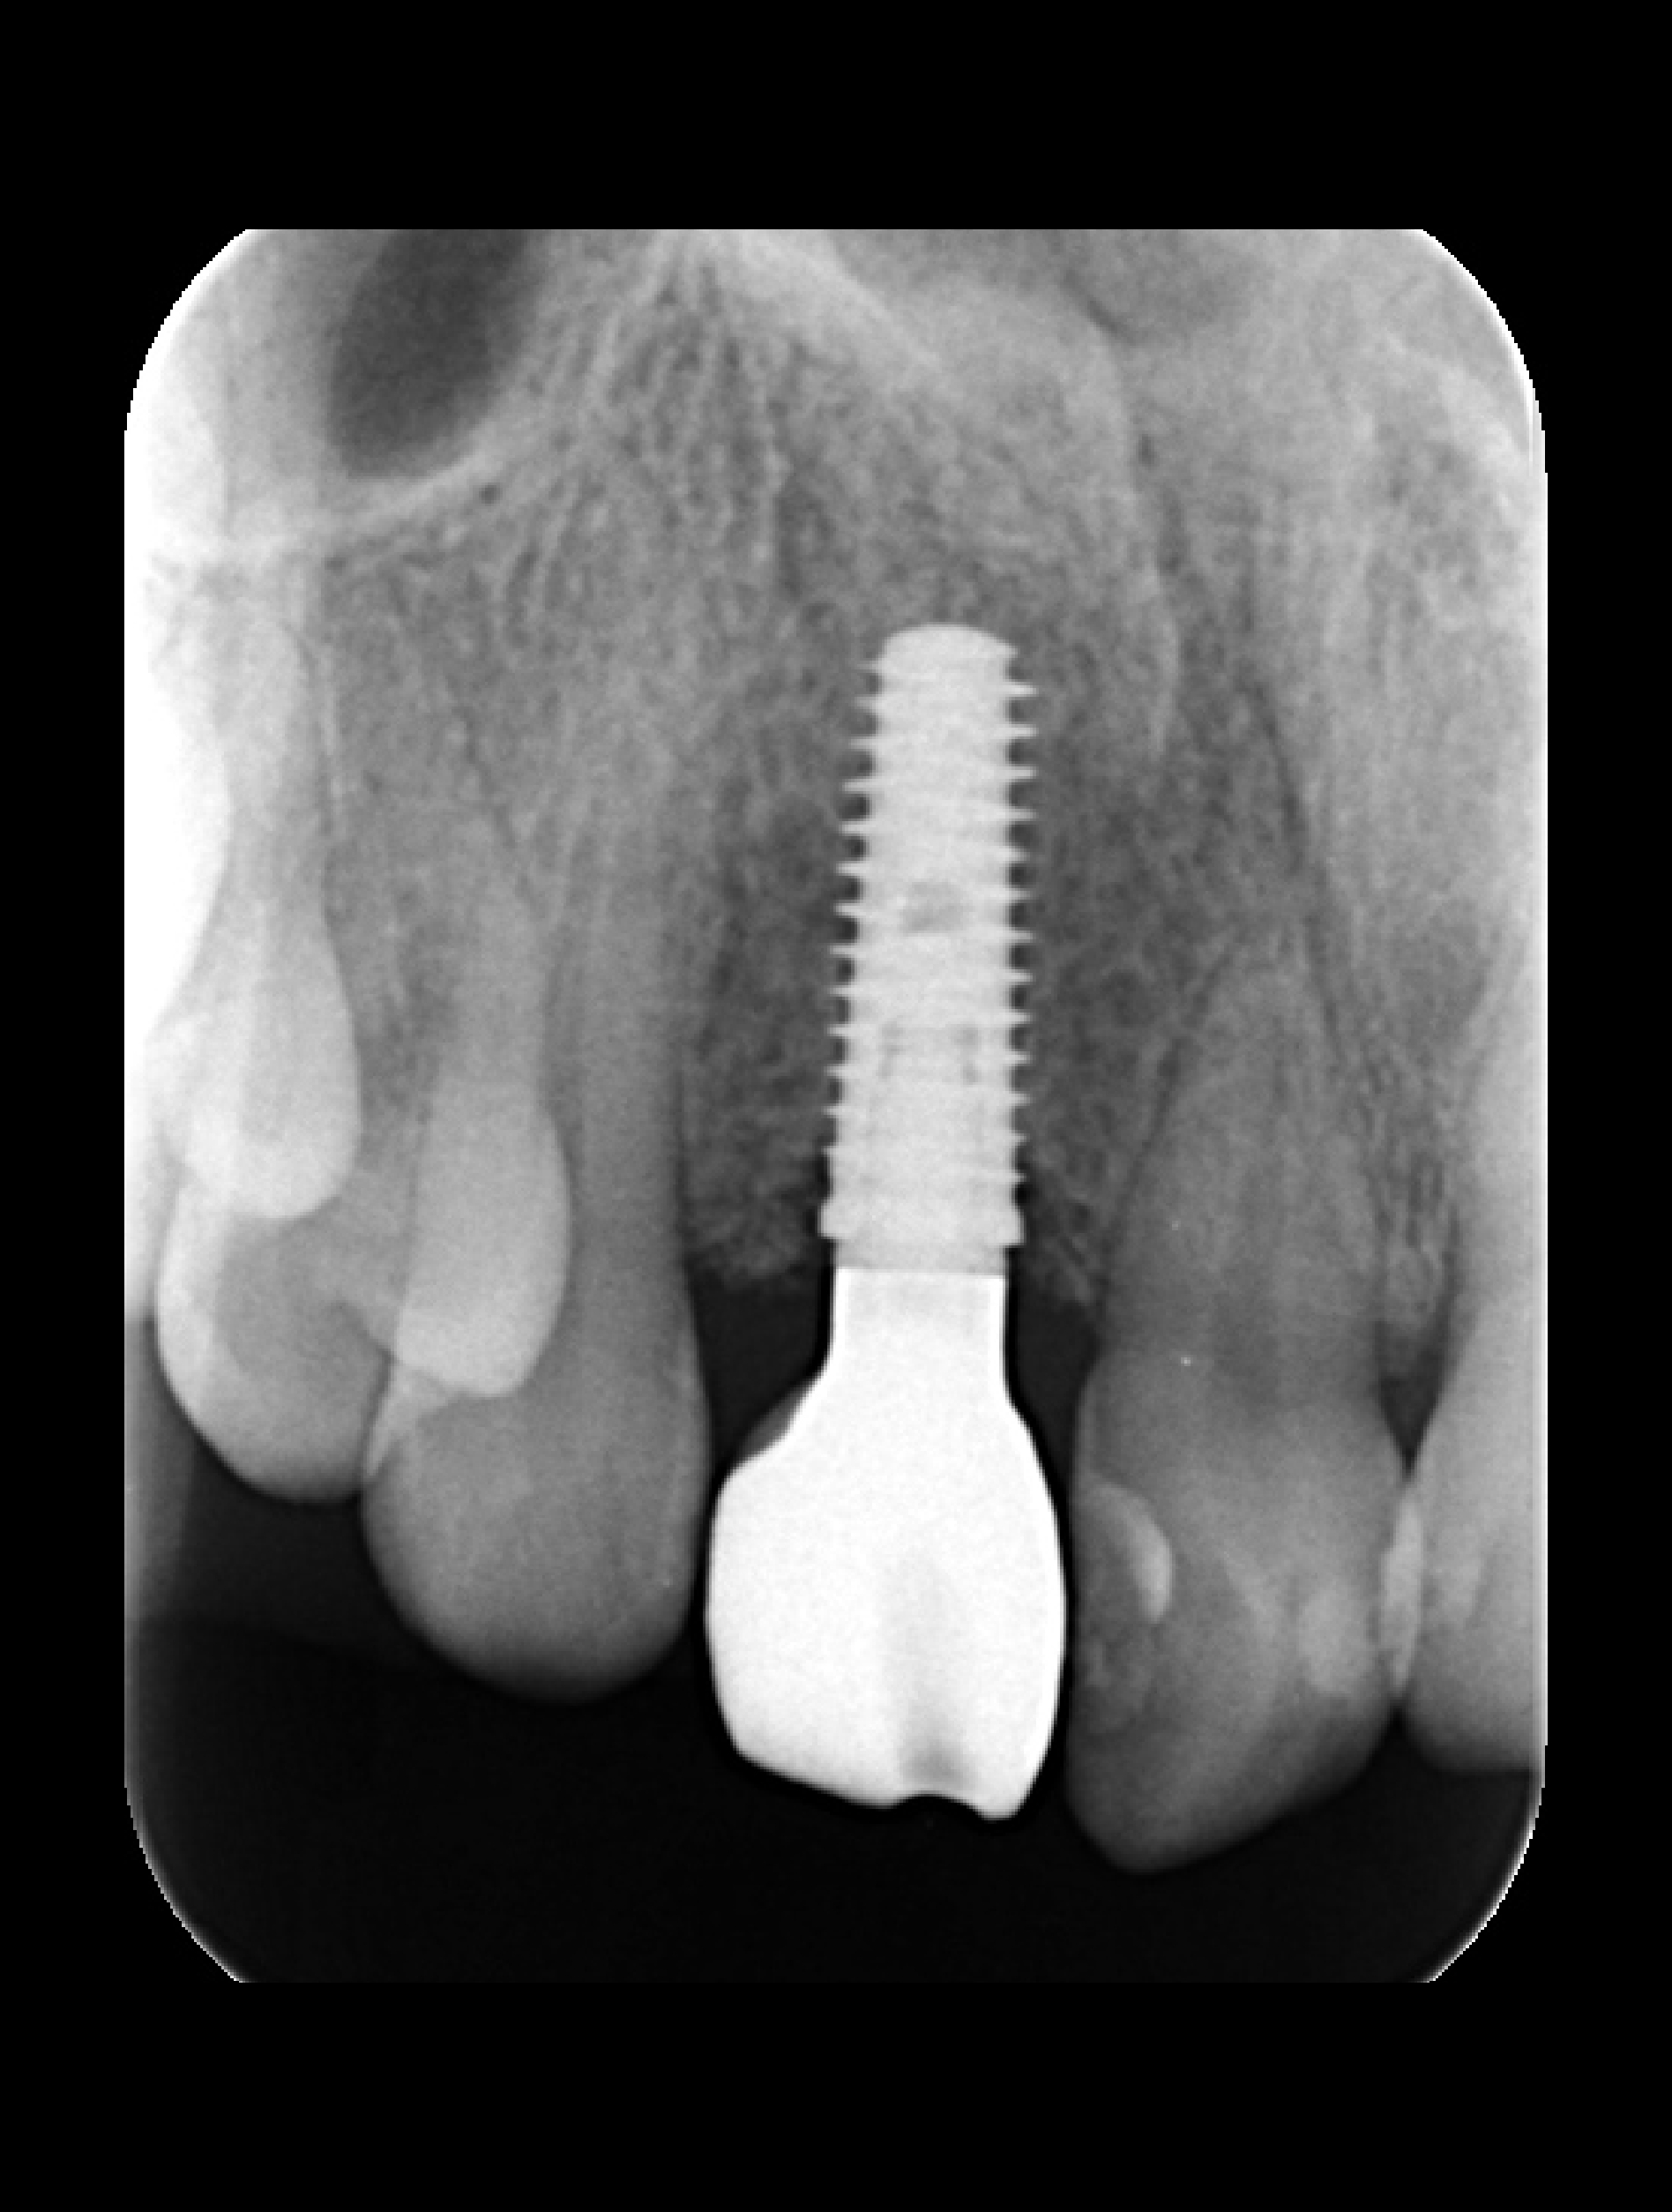

失敗例3 骨が圧倒的に足りていない

これは仮歯を使って、歯の位置をシミュレーションしたときの写真です。圧倒的に骨が足りないことがおわかりいただけると思います。次にもう1枚写真をお見せします。

これが当院に来院した時の状態です。骨が足りないため歯が長くなるだけではなく、高さも不均一です。また、歯茎の形が不自然で審美的に不十分であることがわかります。これらはインプラント・歯周病・審美歯科の技術が高いレベルで揃っていなければ解決できません。